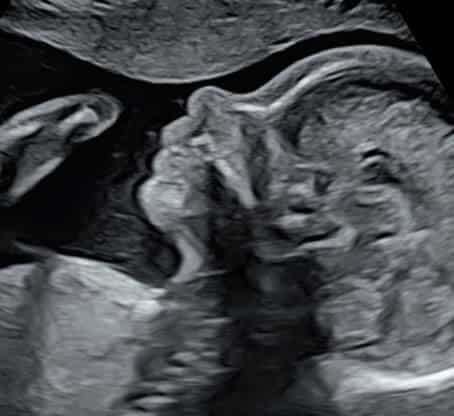

4. L’échographie du 3ᵉ trimestre (32 à 33 SA)

Cette dernière échographie permet de vérifier la croissance finale du bébé, sa présentation et de préparer la naissance.

Elle a pour objectifs :

• D’évaluer le poids estimé et la vitalité fœtale

• De contrôler la position du bébé (tête en bas, siège…)

• De vérifier la position du placenta et le liquide amniotique

• De s’assurer que tout est favorable à un accouchement dans de bonnes condition

C’est souvent la dernière image avant la rencontre réelle.